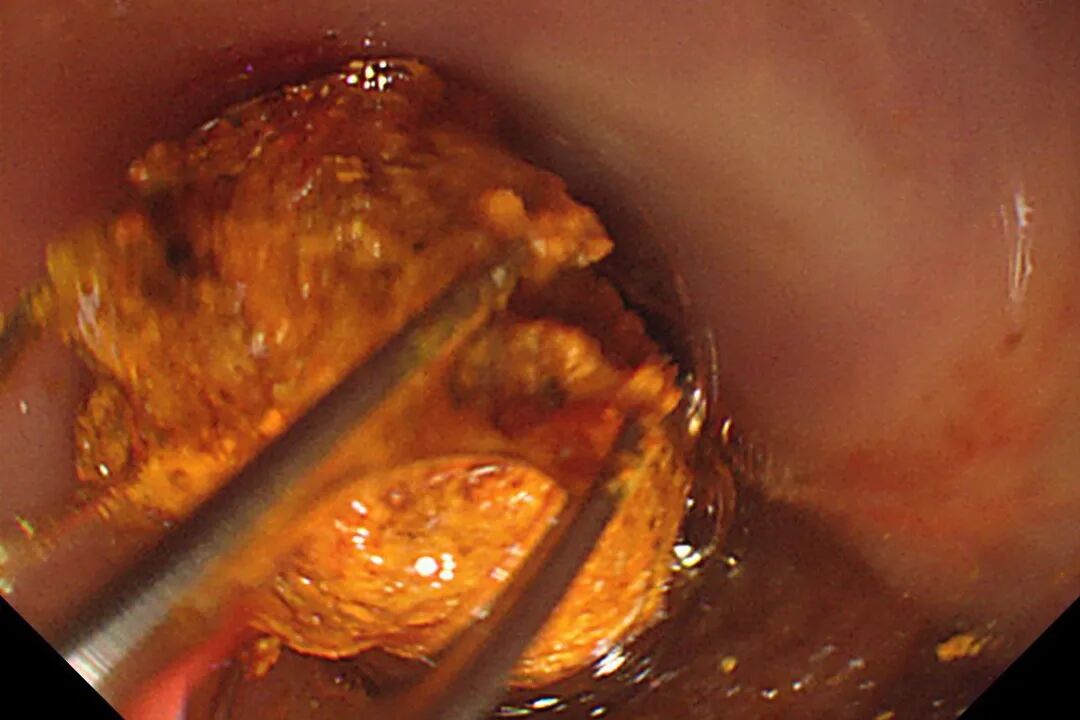

B-II式术后胃-输入袢

术中胃镜戴透明粘膜吸套进镜,可见胃、十二指肠、空肠呈B-II式术后改变,吻合口发红。经团队仔细查找,于输入袢找到十二指肠大乳头,插入三腔括约肌切开刀,并顺利将导丝送入胆总管。造影验证,可见胆总管明显扩张,直径最宽处约16mm,中段见一长条形结石影,约13x12mm。切开乳头后,扩张乳头括约肌及胆总管括约肌,用特制取石导管及取石网篮取出大量黄色块状结石及碎渣样结石。术后置入鼻胆引流管引流,顺利结束手术